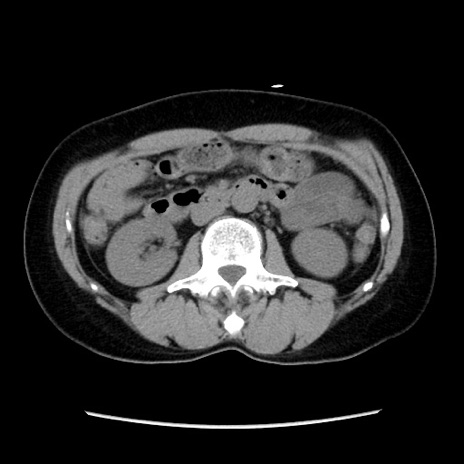

症例10(横断像)

【症例】 50歳代女性

【主訴】 腹痛

【現病歴】前日生レバーを食べた。今朝に排便あり。 昼前に突然発症の腹痛を生じ、当院救急外来を受診した。

【既往歴】 子宮筋腫にてで子宮全摘後

【身体所見】 意識清明、腹部:平坦、軟、下腹部やや左を中心に圧痛・反跳痛あり、筋性防御あり

【データ】WBC 7800、CRP 0.07